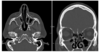

56-årig mand der gennem flere år har haft intermitterende flåd fra næsen. Der er foretaget CT-scanning af bihulerne uden IV-kontrast. Hvilket udsagn stemmer bedst overens med fundene på CT-scanningen. (Obs! Kun ét svar skal være korrekt!)

- a. Intet abnormt

- b. Bilateral kronisk sinuit i sinus sphenoidalis

- c. Bilateral kronisk sinuit i sinus maxillaris med reaktiv ossøs fortykkelse primært på venstre side

- d. Ekspansiv forandring i sinus maxillaris dxt, bør udredes med supplerende MR- eller PET-scanning

- e. Højresidig silent-sinus syndrome samt venstresidig kronisk sinuit i sinus maxillaris

c. Bilateral kronisk sinuit i sinus maxillaris med reaktiv ossøs fortykkelse primært på venstre side